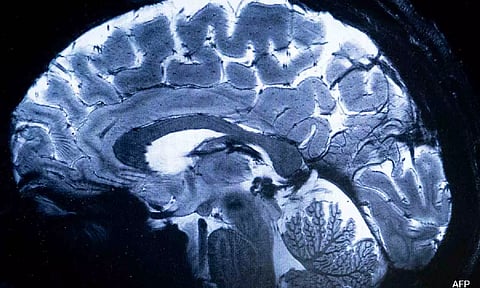

SACLAY [France]: The world's most powerful MRI scanner has delivered its first images of human brains, reaching a new level of precision that is hoped will shed more light on our mysterious minds -- and the illnesses that haunt them.

"We have seen a level of precision never reached before at CEA," said Alexandre Vignaud, a physicist working on the project.

This power allows the machine to scan images with 10 times more precision than the MRIs commonly used in hospitals, whose power does not normally exceed three teslas.

On a computer screen, Vignaud compared images taken by this mighty scanner, dubbed Iseult, with those from a normal MRI.

"With this machine, we can see the tiny vessels which feed the cerebral cortex, or details of the cerebellum which were almost invisible until now," he said.